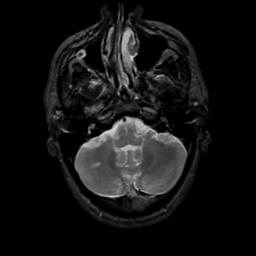

MR Study #8, March 31, 1991 -- Slice #10

[Home][Help][Clinical][Tour 1][Tour 2] Slice 10